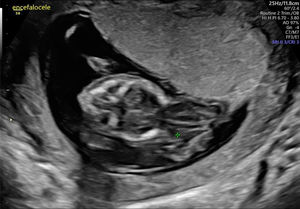

En la ecografía realizada al día siguiente en la consulta se objetivó un feto único en situación transversa izquierda con movimientos cardíacos fetales positivos. Se visualizó un encefalocele occipital de gran tamaño (fig. 1), con un defecto de la calota a nivel occipital y herniación importante de las estructuras cerebrales. En el extremo del encefalocele se objetivó una banda amniótica conectada al amnios (fig. 2). Asimismo, presentaba una ectopia cordis, con un importante defecto de la formación de la pared torácica anterior, ubicándose el corazón en el exterior de la caja torácica. En el estudio del corazón se visualizó que presentaba hipoplasia del ventrículo izquierdo. También se observó un gran defecto a nivel de la pared abdominal anterior, presentando gastrosquisis de gran cantidad de asas de intestino delgado y gran parte del hígado (fig. 3). Por último, a nivel de la columna se visualizó una cifoescoliosis severa a nivel lumbar (fig. 4). A nivel de placenta y anejos, la placenta se encontraba insertada en la cara anterior del útero con ecogenicidad acorde a la edad gestacional. En lo referente al amnios, este presentaba un fallo en la fusión con el corion (fig. 5). La cantidad de líquido amniótico era normal. No se encontraron otros hallazgos en la exploración ecográfica.